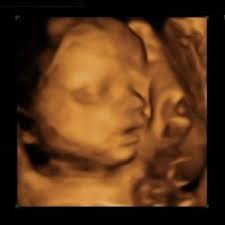

Wir erklären die einzelnen SSW und zeigen was in jeder Schwangerschaftswoche im Körper geschieht. Entwicklungsstand des Fötus 29SSW Inzwischen wiegt dein Baby um die 1200 Gramm und ist nun ca. Schwangerschaftswoche können die üblichen Beschwerden wie Rückenschmerzen Beschwerden durch die heftigen Kindsbewegungen sowie geschwollene und schmerzende Beine auftreten.

Dadurch nimmt auch das Gehirnvolumen noch einmal zu und das Skelett des Kopfes wächst dabei mit. Schwangerschaftswoche SSW 29 Baby und Bauch wachsen und wachsen. In der 29.

Gehirn und Nervensystem entwickeln sich in dieser Woche noch einmal deutlich weiter und funktionieren differenzierter. Schwangerschaftswoche auf die Welt kommen überleben.

Schwangerschaftswoche Der Gehörsinn entwickelt sich weiter und dein Baby kann die Augen öffnen. Schwangerschaftswoche über ständigen Hunger verspüren aber gleichzeitig ein Völlegefühl. Auch wenn es bei manchen Frauen um den Zeitpunkt herum zu einer kleinen Schmierblutung die sog. SSW wachsen auch die Wimpern und Augenbrauen Ihres Kindes. Tritt das Baby in die letzte intensive Phase von Längenwachstum und Gewichtszunahme ein. Schwangerschaftswoche Der Gehörsinn entwickelt sich weiter und dein Baby kann die Augen öffnen. Großen Vorsorge was der Krümel aktuell wiegt und wie es ihm geht. Das Gehirn wird aktiver. SSW Schwangerschaftswoche ist das Baby ungefähr 39 Zentimeter lang SFL und wiegt circa 1250 Gramm.